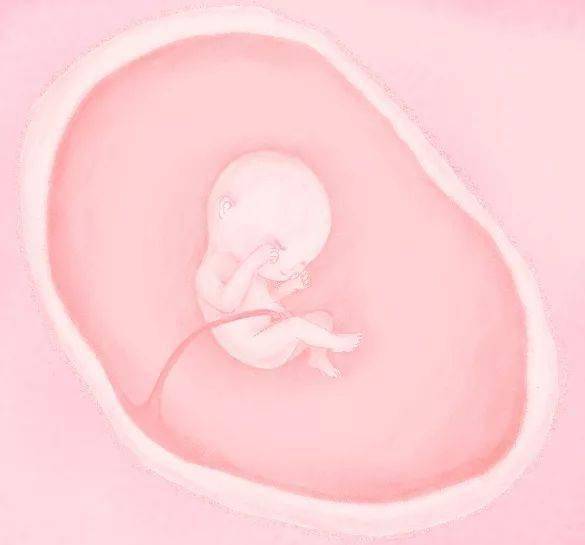

▲ 孕 1 月

排卵,卵子与精子结合,受精卵形成,胚泡植入子宫内膜,胚胎形成,受精卵不断分裂,一部分形成大脑,其余形成神经组织。神经管闭合。